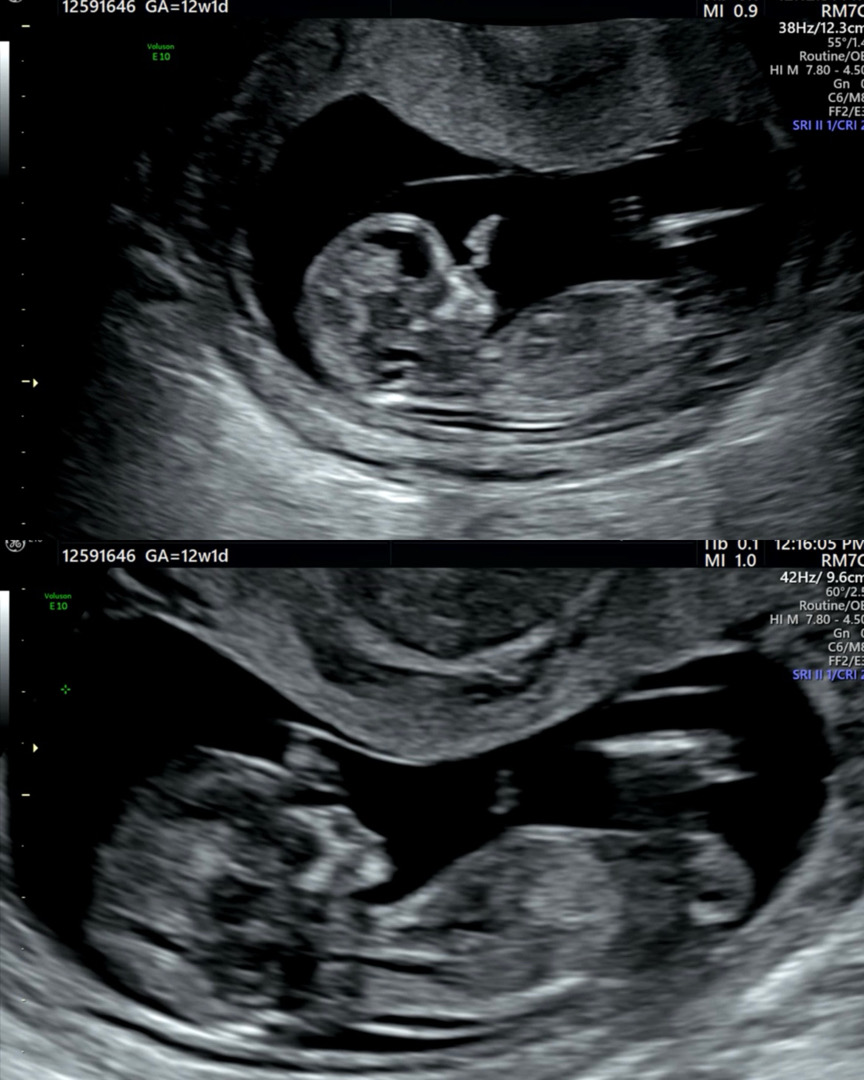

12주차 성별 딸일까요 아들일까요??

각도가 잘 보이는지 모르겠네요ㅠㅠ 어떤 성별일지 넘 궁금해요~!!